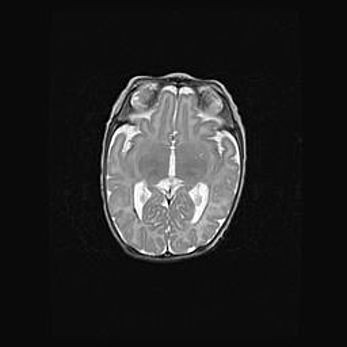

Неполная лизэнцефалия (пахигирия). Открытая гидроцефалия.

Возраст: 17 дней

Вес: 3110 г

Пол: мужской

Окружность головы: 33,5 см

Срок гестации: 35-36 недель

Лизэнцефалия—недоразвитие корковой пластинки и мозговых извилин в результате нарушения миграции нейронов коры. Поверхность мозговых полушарий гладкая. Микроскопически выявляется отсутствие нормальных слоев коры и скопление групп нейронов в подкорковом белом веществе.

Пахигирия—уменьшение числа вторичных извилин. В пораженном полушарии нервные клетки образуют толстый недифференцированный слой с неправильно расположенными нервными волокнами и группами гетеротопных клеток. Нервные клетки незрелые. Белое вещество истончено. При этом нередко аномально развит корково-спинномозговой путь.